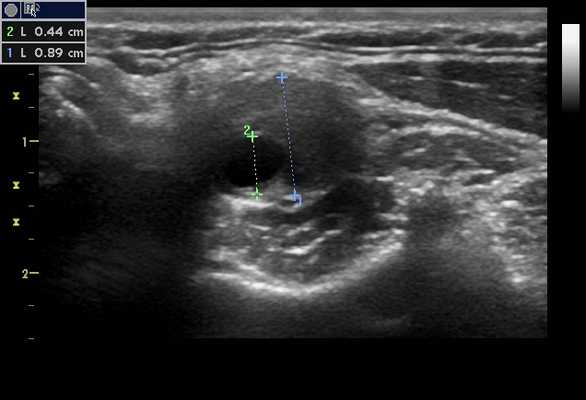

Стеноз, вызванный гигантоклеточным или височным артериитом, дает типичные результаты ультразвукового исследования, связанные с любым стенозом. Основным инструментом, используемым для определения стеноза, будет очаговое увеличение ПСС, которая в два раза превышает значение ПСС в соседнем более проксимальном сосуде, указывает, по крайней мере, на стеноз 50%. Этот критерий применим к большинству артерий. На изображении в режиме B · гигантоклеточный артериит часто выглядит как гипоэхогенное концентрическое утолщение стенки. Это утолщение может происходить на длинном сегменте сосуда и приводить к сужению просвета артерии: кроме того, может присутствовать анэхогенная зона, окружающая сосуд, создавая «ореол» вокруг сосуда. Считается, что это происходит из-за инфильтрации лейкоцитов. «Ореол» или «хало» должен присутствовать как в поперечной, так и в сагиттальной плоскости изображения.